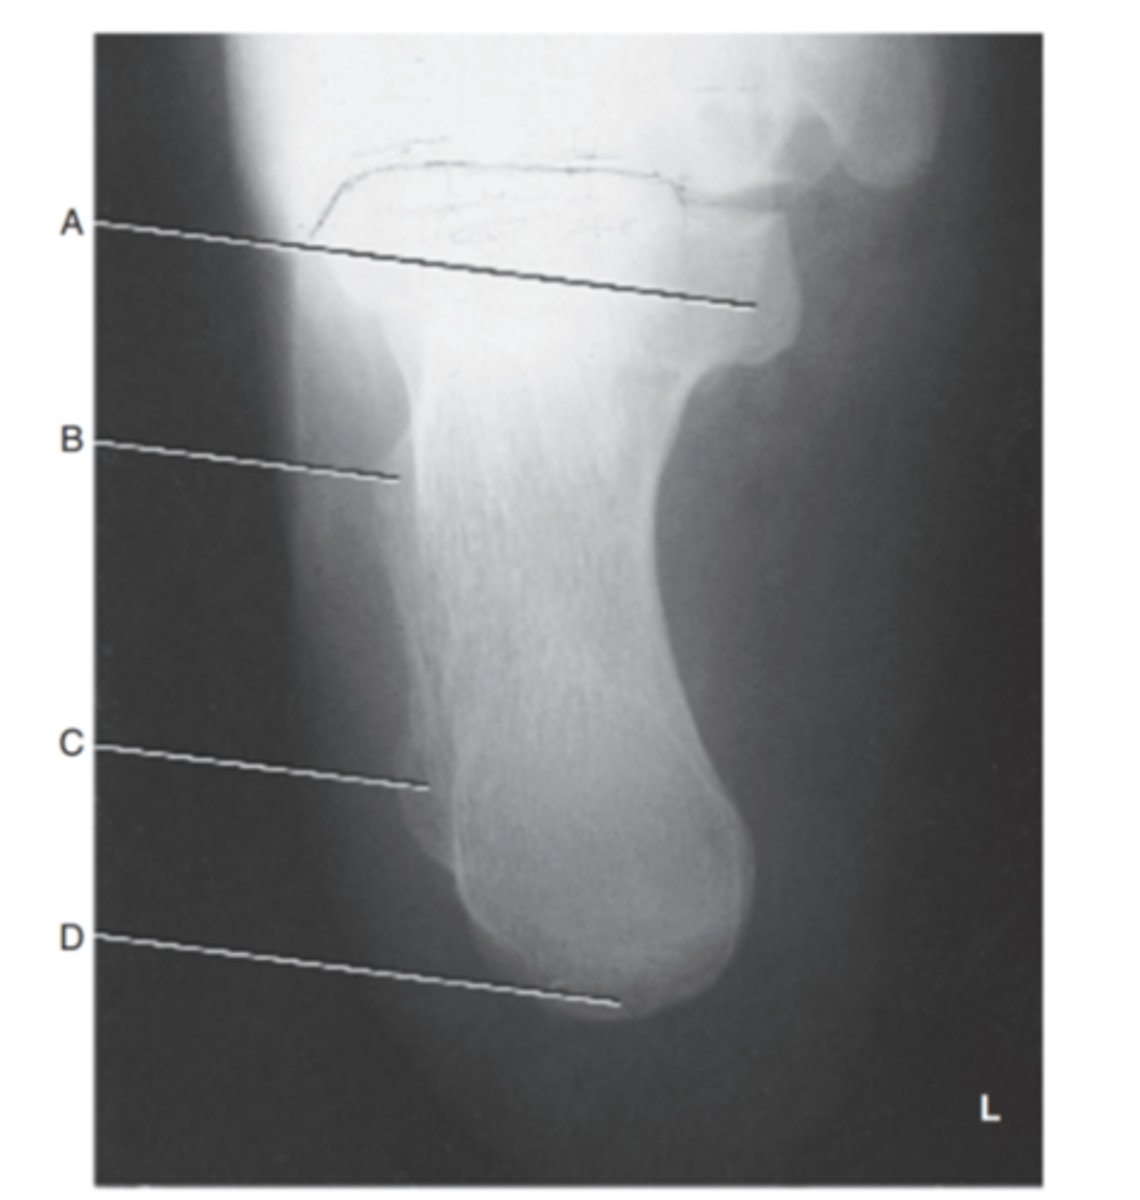

(Axial Plantodorsal calcaneus) what is A?

sustentaculum tali

what is B?

trochlear process

what is C?

lateral process

what is D?

tuberosity